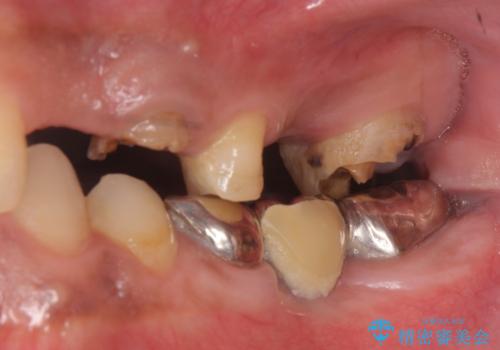

- 歯がない左側でものが咬めず、右側で咬むと歯が痛むので診て欲しいといらっしゃった方の症例です。

根尖病変が認められる歯は再根管治療を行い、歯根が破折していた左上4は抜歯しました。

インプラントは希望されなかったため、左側は1番から7番のロングスパンブリッジによる補綴を行いました。